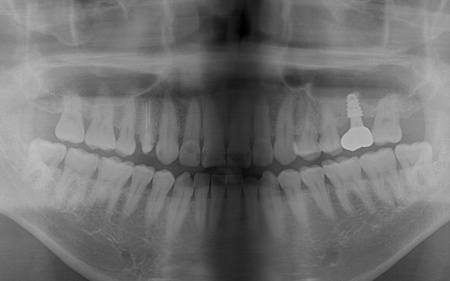

③温存が難しい左上奥歯(第1大臼歯)は抜き、骨を再生させる処置「GBR(骨造成)」を行ったのち、人工歯根を埋め込む「インプラント治療」により噛む機能を回復させます。

左上奥歯1本は抜き、GBRで骨を再生させたのち、インプラントを埋入します。

インプラントに装着する人工歯の素材には、自費診療の白いセラミックを選択しました。